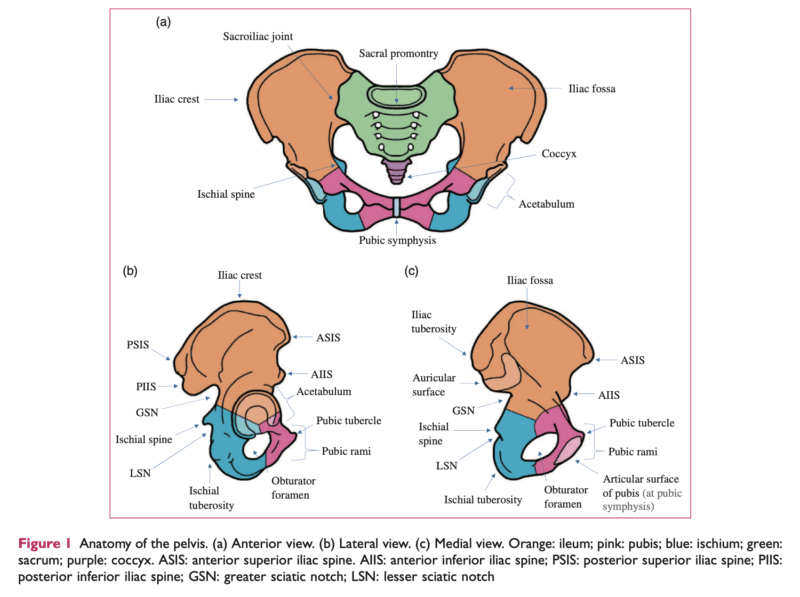

恥骨は, 赤で示された骨です.

左右の恥骨は下腹部前方で恥骨結合(Pubic symphysis)という軟骨でつながっています.

そのうちのお1人は, 1月から脚の付け根の痛みがあったので, 一昨日先輩医師の整形外科クリニックを受診された中高年の患者さんでした. X線写真が撮像された結果, 骨盤の前方にある骨(恥骨)(上図参照)に異常が認められたため, 当科に紹介されました.